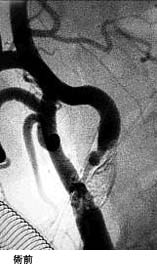

破裂脳動脈瘤に対するコイル塞栓術GODコイルだとちょっと古いので、コイル塞栓術とする方が良いのではないかと思います。

術後 コイルにより動脈瘤が写らなくなりました。